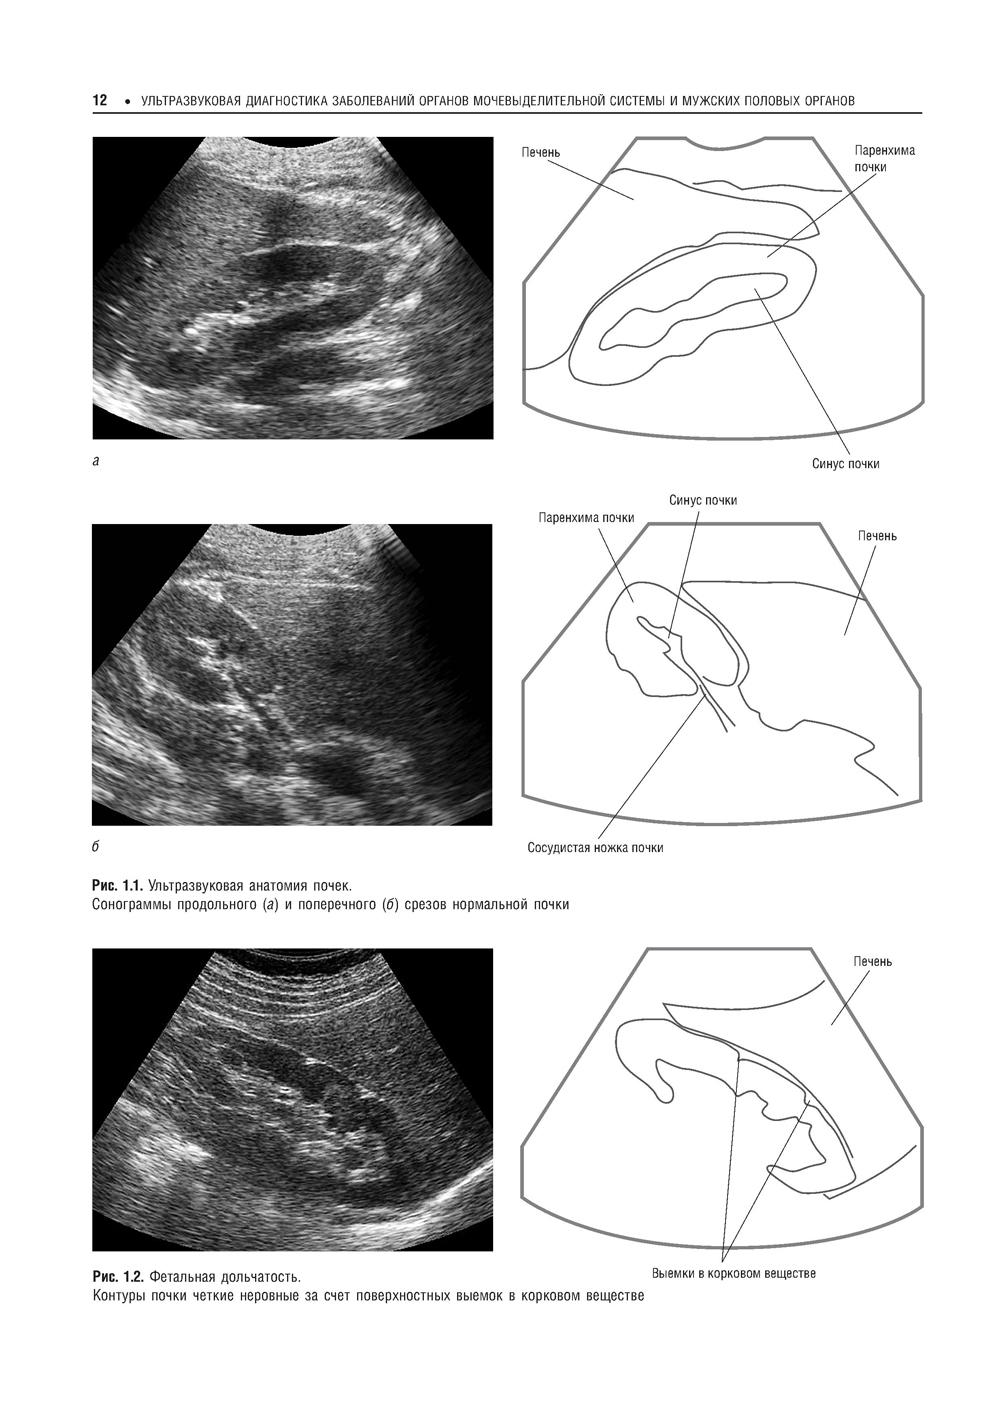

Второй том руководства рассказывает о применении различных методик ультразвукового исследования в диагностике заболеваний почек, мочеточников, мочевого пузыря и мочеиспускательного канала, мужских половых органов и надпочечников. Описывается нормальная ультразвуковая анатомия соответствующих органов, клиника и УЗ-семиотика наиболее часто встречающихся заболеваний и патологий. Отдельная глава посвящена неотложной УЗ-диагностике при острых заболеваниях и повреждениях мочевых органов. Издание адресовано слушателям, обучающимся в системе послевузовского профессионального дополнительного образования, а также специалистам по лучевой диагностике, врачам, работающим в кабинетах и отделениях ультразвуковой диагностики.